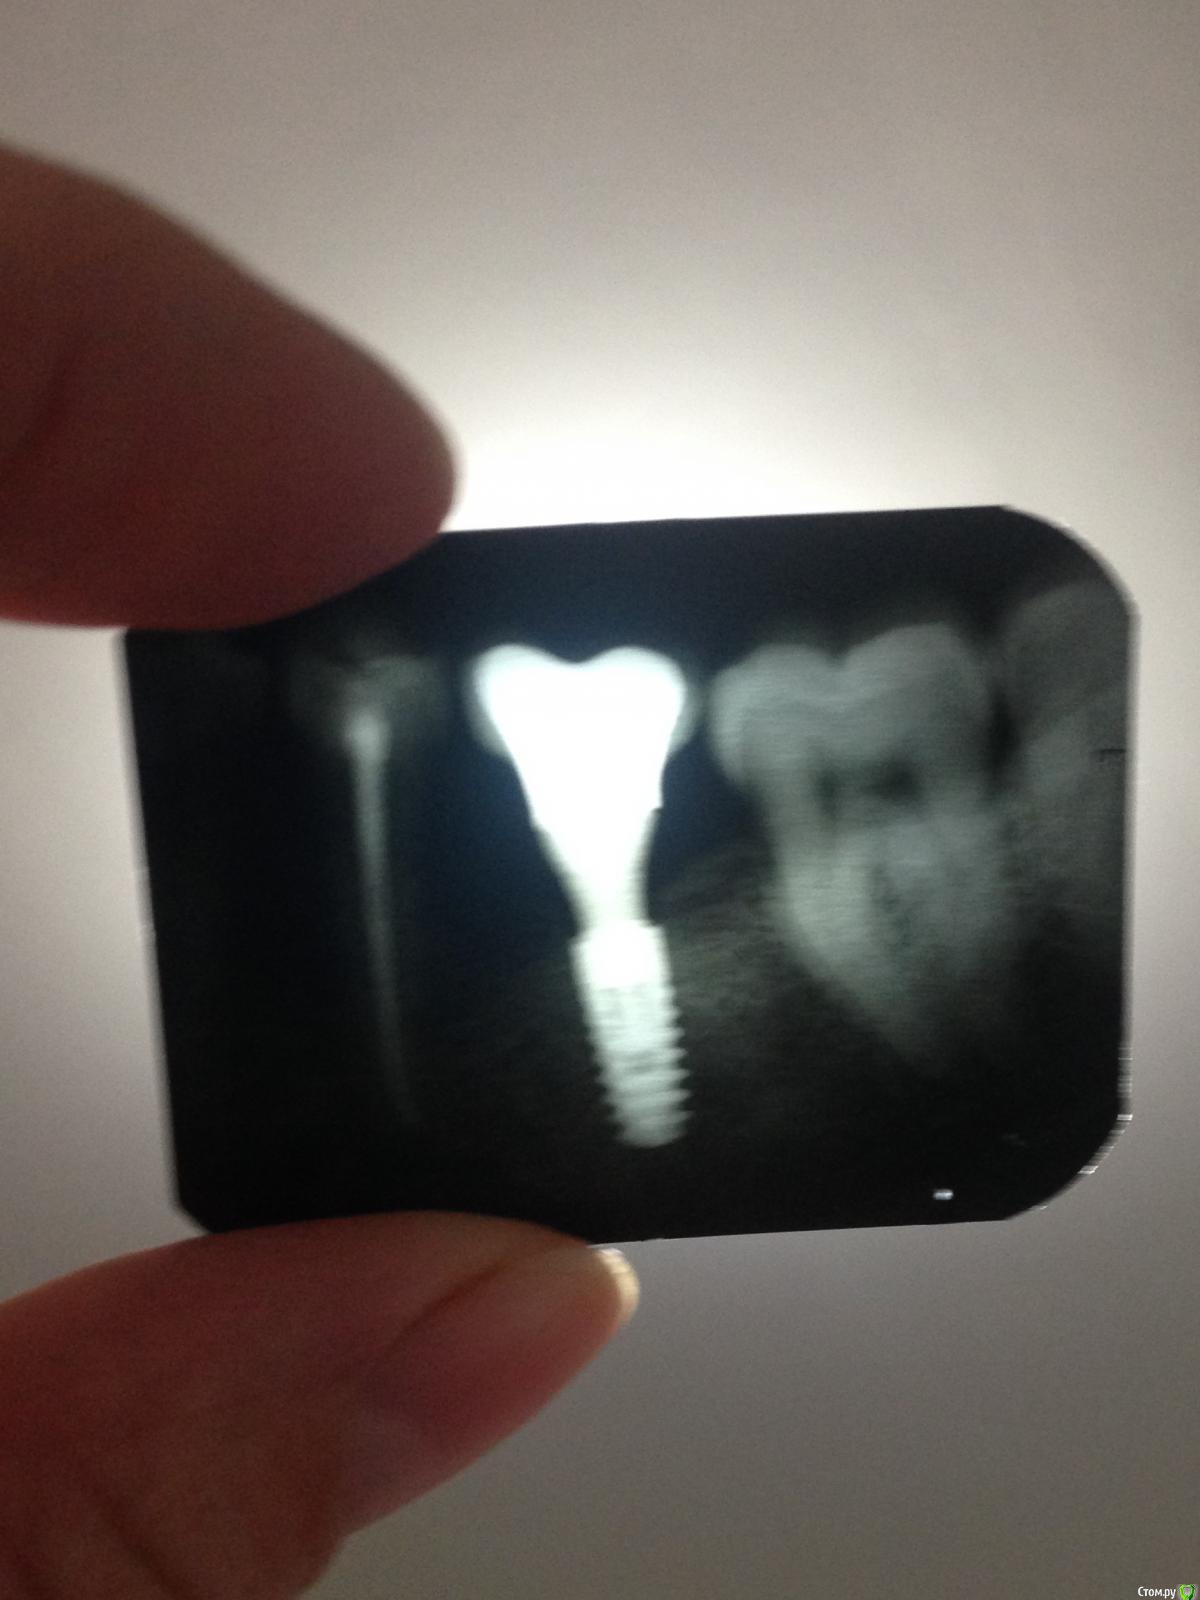

Ирина А. Опубликовано 12 мая, 2016 Поделиться Опубликовано 12 мая, 2016 (изменено) Добрый день, уважаемые доктора!Вопрос по лечению оголения импланта: стоит лет 5-6, изначально проявилась убыль костной ткани, но в последнее время несколько больше оголился имплант и я стала переживать за соседние зубы, так же появился дискомфорт, так как ощущается даже щекой с закрытым ртом, что есть пустое пространство в районе импланта.Хотелось бы найти грамотного специалиста, способного решить проблему.И узнать варианты решения)Извините за качество фото)Спасибо! Изменено 12 мая, 2016 пользователем Ирина А. Ссылка на комментарий

Aquarius Опубликовано 12 мая, 2016 Поделиться Опубликовано 12 мая, 2016 похоже, что цемент под десной, недостаток кератинизированнных тканей, как следствие - хроническое воспаление. 1 Ссылка на комментарий